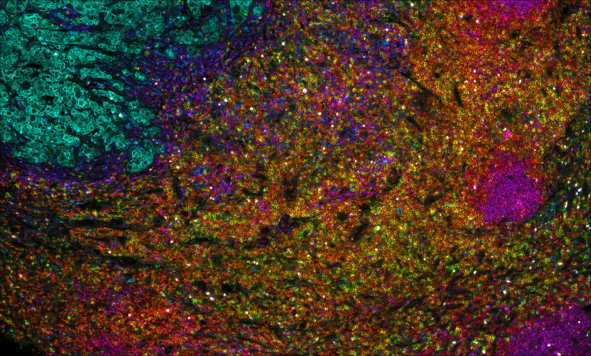

Multiplex immunofluorescence (mIF) is a powerful technique that allows researchers to simultaneously visualize and analyze multiple components of the tissue microenvironment. Multiplexing uses multiple antibodies with fluorescent detection to target specific proteins within the microenvironment, allowing researchers to create a detailed map of the various cells, proteins and their interactions. We offer both low plex and high plex options for mIF which allow you to profile tissues to determine cell phenotypes, their functional state, and cell interactions.